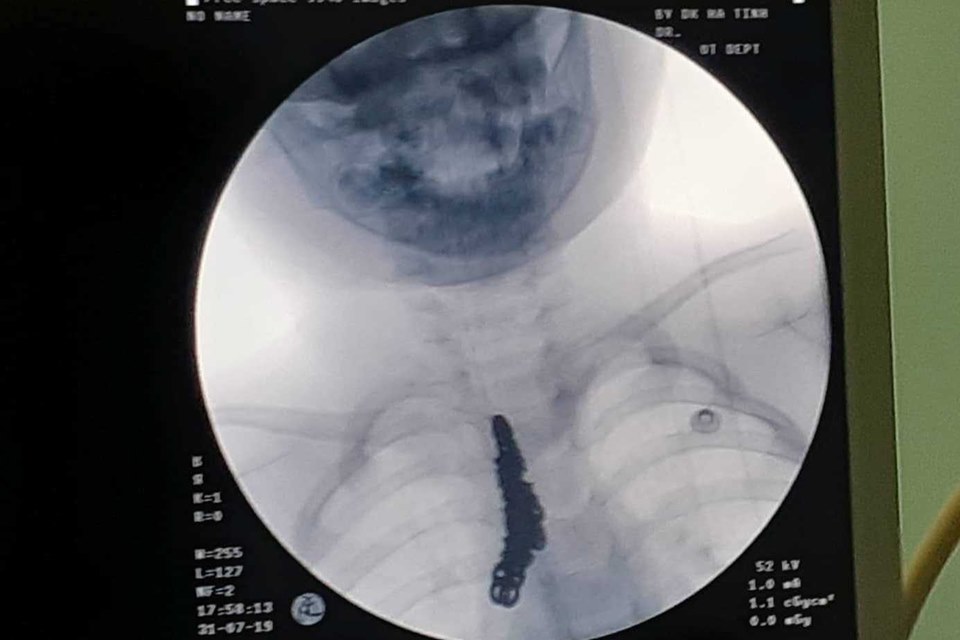

Hình ảnh vòng bạc trong khí phế quản bệnh nhi

Sau khi thăm khám và chụp phim XQ, các bác sỹ phát hiện hình ảnh cản quang bất thường tương ứng khí quản và một phần phế quản gốc bên phải. Kết quả nội soi khí quản phát hiện dị vật nằm ở vị trí nói trên. Ngay lập tức, các bác sỹ đã tiến hành gắp ra 1 sợi dây chuyền bạc có kích thước dài 14cm.